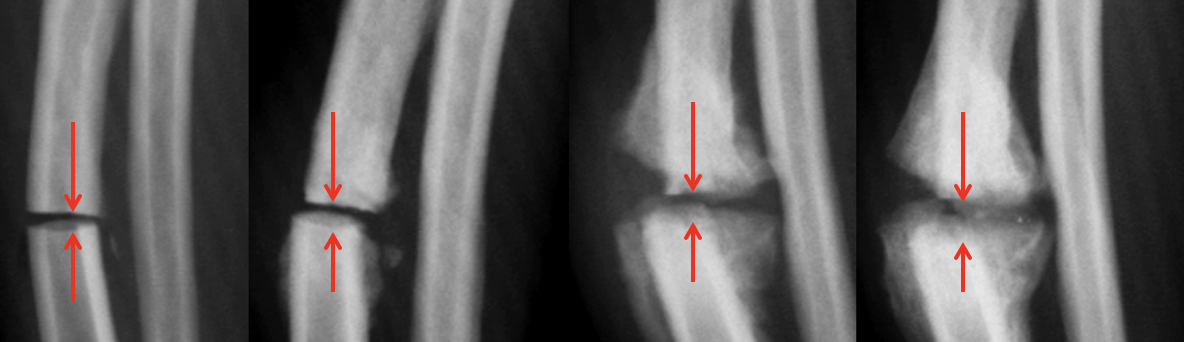

What is shown in these radiographs?

premature distal radial physis closure

-increased radiocarpal joint space

-increased humero-radial joint space

Which physis has closed prematurely in each set of radiographs?

Left: distal ulnar physis

Right: distal radial physis